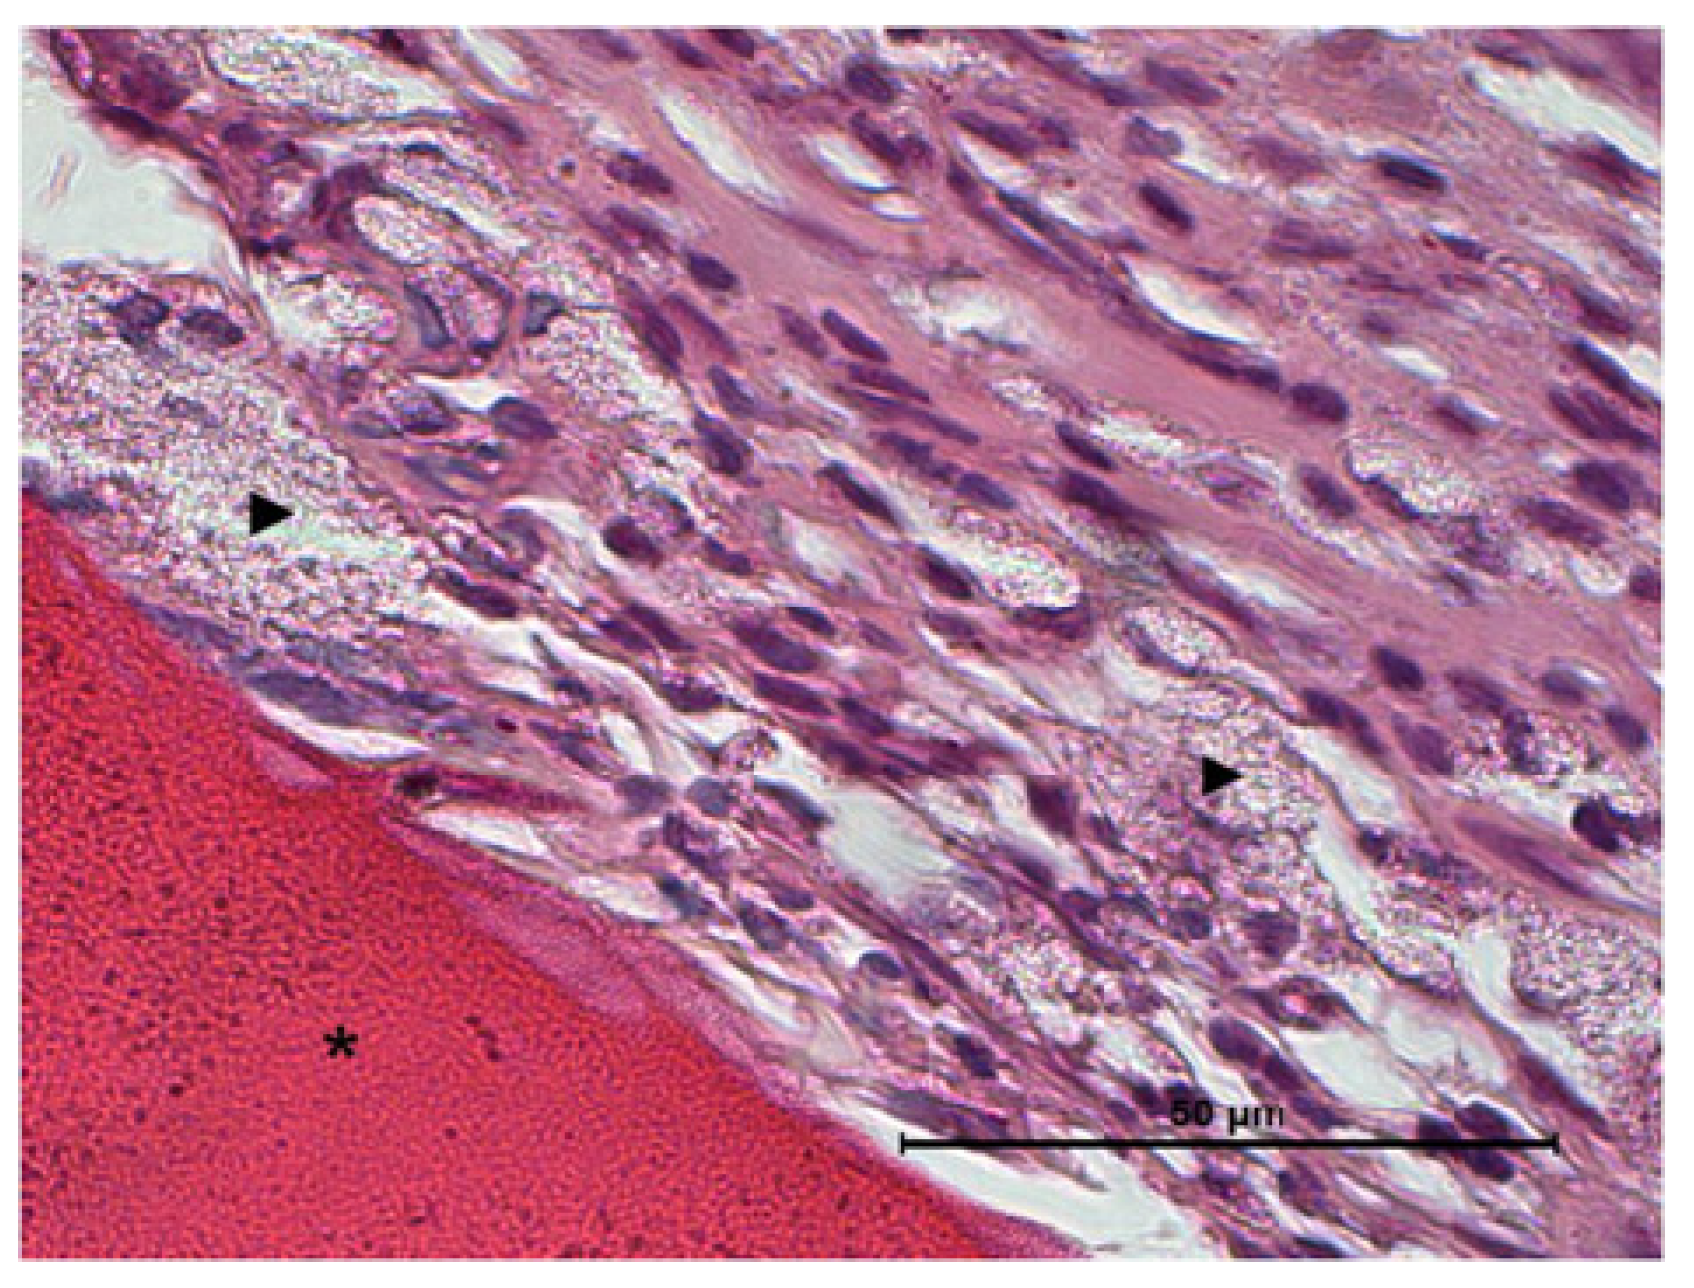

Figure 9.

Histological evaluation of CS/Sol-Si biocomposite at 14 days post-implantation. (a,b) Show at the tissue–biomaterial interface, the replacement of the clot by reparative granulation tissue (#) and formation of woven bone tissue (♦). (c) Shows osseointegrated woven bone tissue (↑). (a–c) Orig. Mag. × 400; H-E stain. (*) chitosan; (►) silica particles.

Fourteen days after the implantation of CS/Sol-Si and CS, there were no acute inflammatory infiltrates or multinucleated giant cells, indicating good biocompatibility of both materials. At the tissue–biomaterial interface, the clot was replaced by reparative granulation tissue with abundant fibroblasts and a new formation of woven bone tissue (immature bone, confirmed by polarized light microscopy), sometimes in close contact with the surfaces of both biomaterials (osseointegration) (Figure 8 and Figure 9). It is worth highlighting that histologically, larger areas of osseointegration were observed with CS/Sol-Si than with CS.

Masson’s trichrome stain clearly shows how the reparative granulation tissue (red) is progressively replaced by woven bone tissue (blue) (Figure 10b,c).